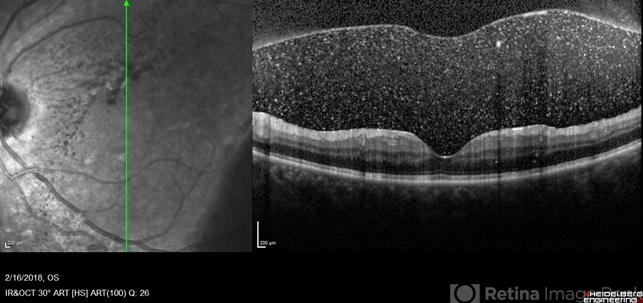

- vitreous hemorrhage, optical coherence tomography (OCT), Heidelburg Spectralis, proliferative diabetic retinopathy (PDR), diabetes, left eye, posterior vitreous detachment

- SD-OCT of a 35-year-old female presenting with a vitreous hemorrhage of her left eye. Patient has active proliferative diabetic retinopathy, as well as a completed posterior vitreous detachment in the left eye.